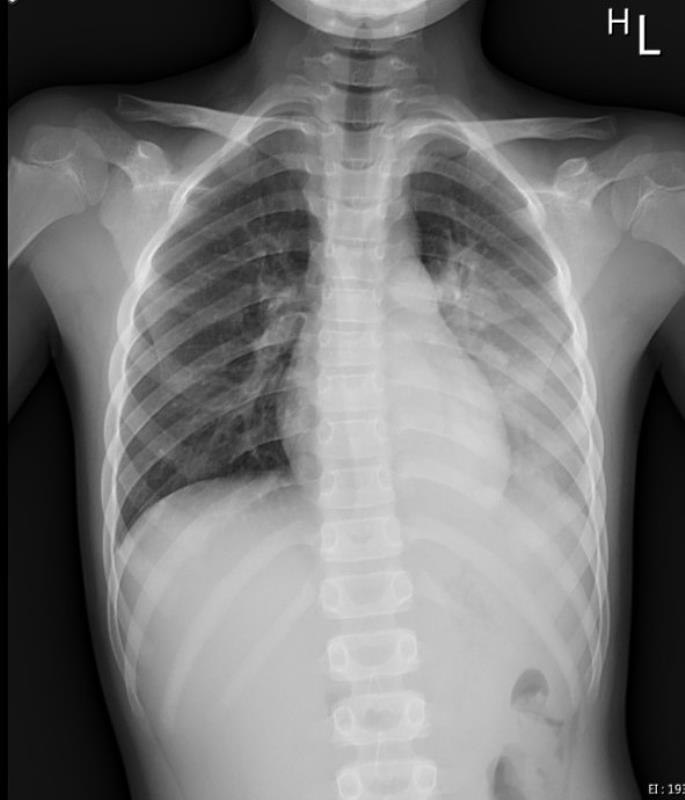

一名八歲男童因呼吸道融合病毒(RSV)合併肺炎鏈球菌及鼻病毒的感染,造成左側大葉性肺炎,就醫檢查胸部X光發現左邊肺部幾乎白了,住進花蓮慈院兒科加護病房接受治療。陳明群主任指出,在過去的兒科臨床案例中,這種RSV造成年紀較大的孩子發生肺炎的案例是相對少見的,大多都是四五歲以下的小小孩免疫系統還未成熟且細支氣管較細小,被病毒攻擊時才會這麼嚴重。陳明群舉例,一般兒童原本會在成長過程中偶爾得到小感冒,讓體內的免疫系統循序漸進、慢慢累積對疾病的抵抗力,這是身體自然建立防禦的過程;但過去三年間孩子們被保護得很好,戴口罩、勤洗手、保持社交距離等防疫措施更大幅隔絕飛沫傳染細菌及病毒的可能,因此當解除防疫限制後,身體一下子接觸到多種從未碰過的病毒,就像許多小感染的威力一次聚集發作,造成比普通感冒更為嚴重的症狀,即「免疫負債」效應,讓即便已上小學年紀的孩子也難免除於多重呼吸道細菌及病毒的攻擊。